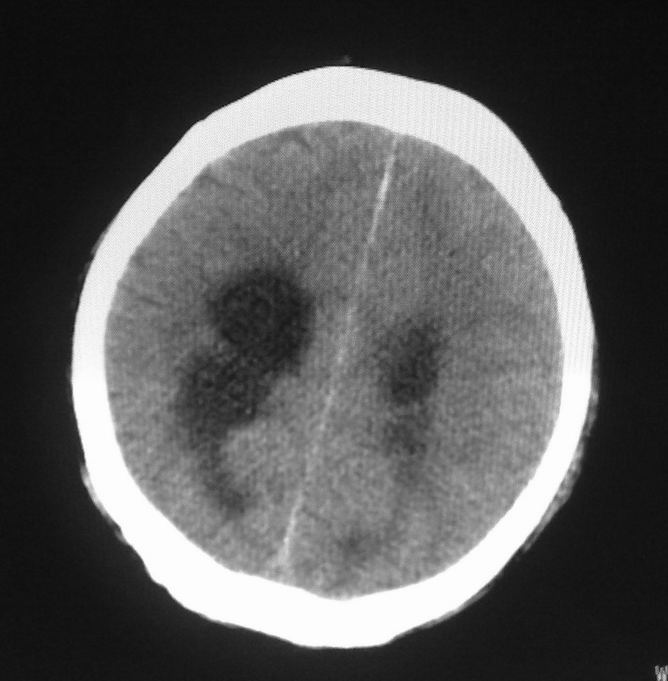

标题: CT24862:男,61岁,发热,有脑出血病史。 [打印本页]

男,61岁,发热,有脑出血病史。

右侧基底节,放射冠软化灶,胼胝体发育不良 脑积水原因待查。

右侧基底节及放射冠软化灶,脑积水,四脑室显示不清,导水管梗阻?建议mri!

梗阻性脑积水,出血后粘连所致

1)右侧基底节区、右侧放射冠及右侧丘脑软化灶。2)脑积水。